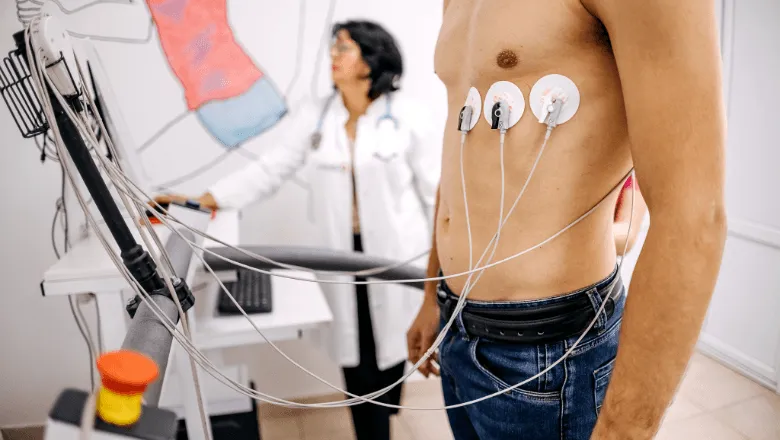

ECG Test in Dubai: Cost, Types, Results & What to Expect (2026)

Complete guide to ECG (EKG) tests in Dubai from AED 100. Resting ECG, Holter monitor, stress ECG. Results explained, walk-in testing available at DCDC.

Cardiac Stress Test in Dubai: Cost, Procedure & What to Expect (2026)

Complete guide to cardiac stress tests (TMT/treadmill test) in Dubai from AED 800. Bruce Protocol stages, results interpretation, preparation, and costs.